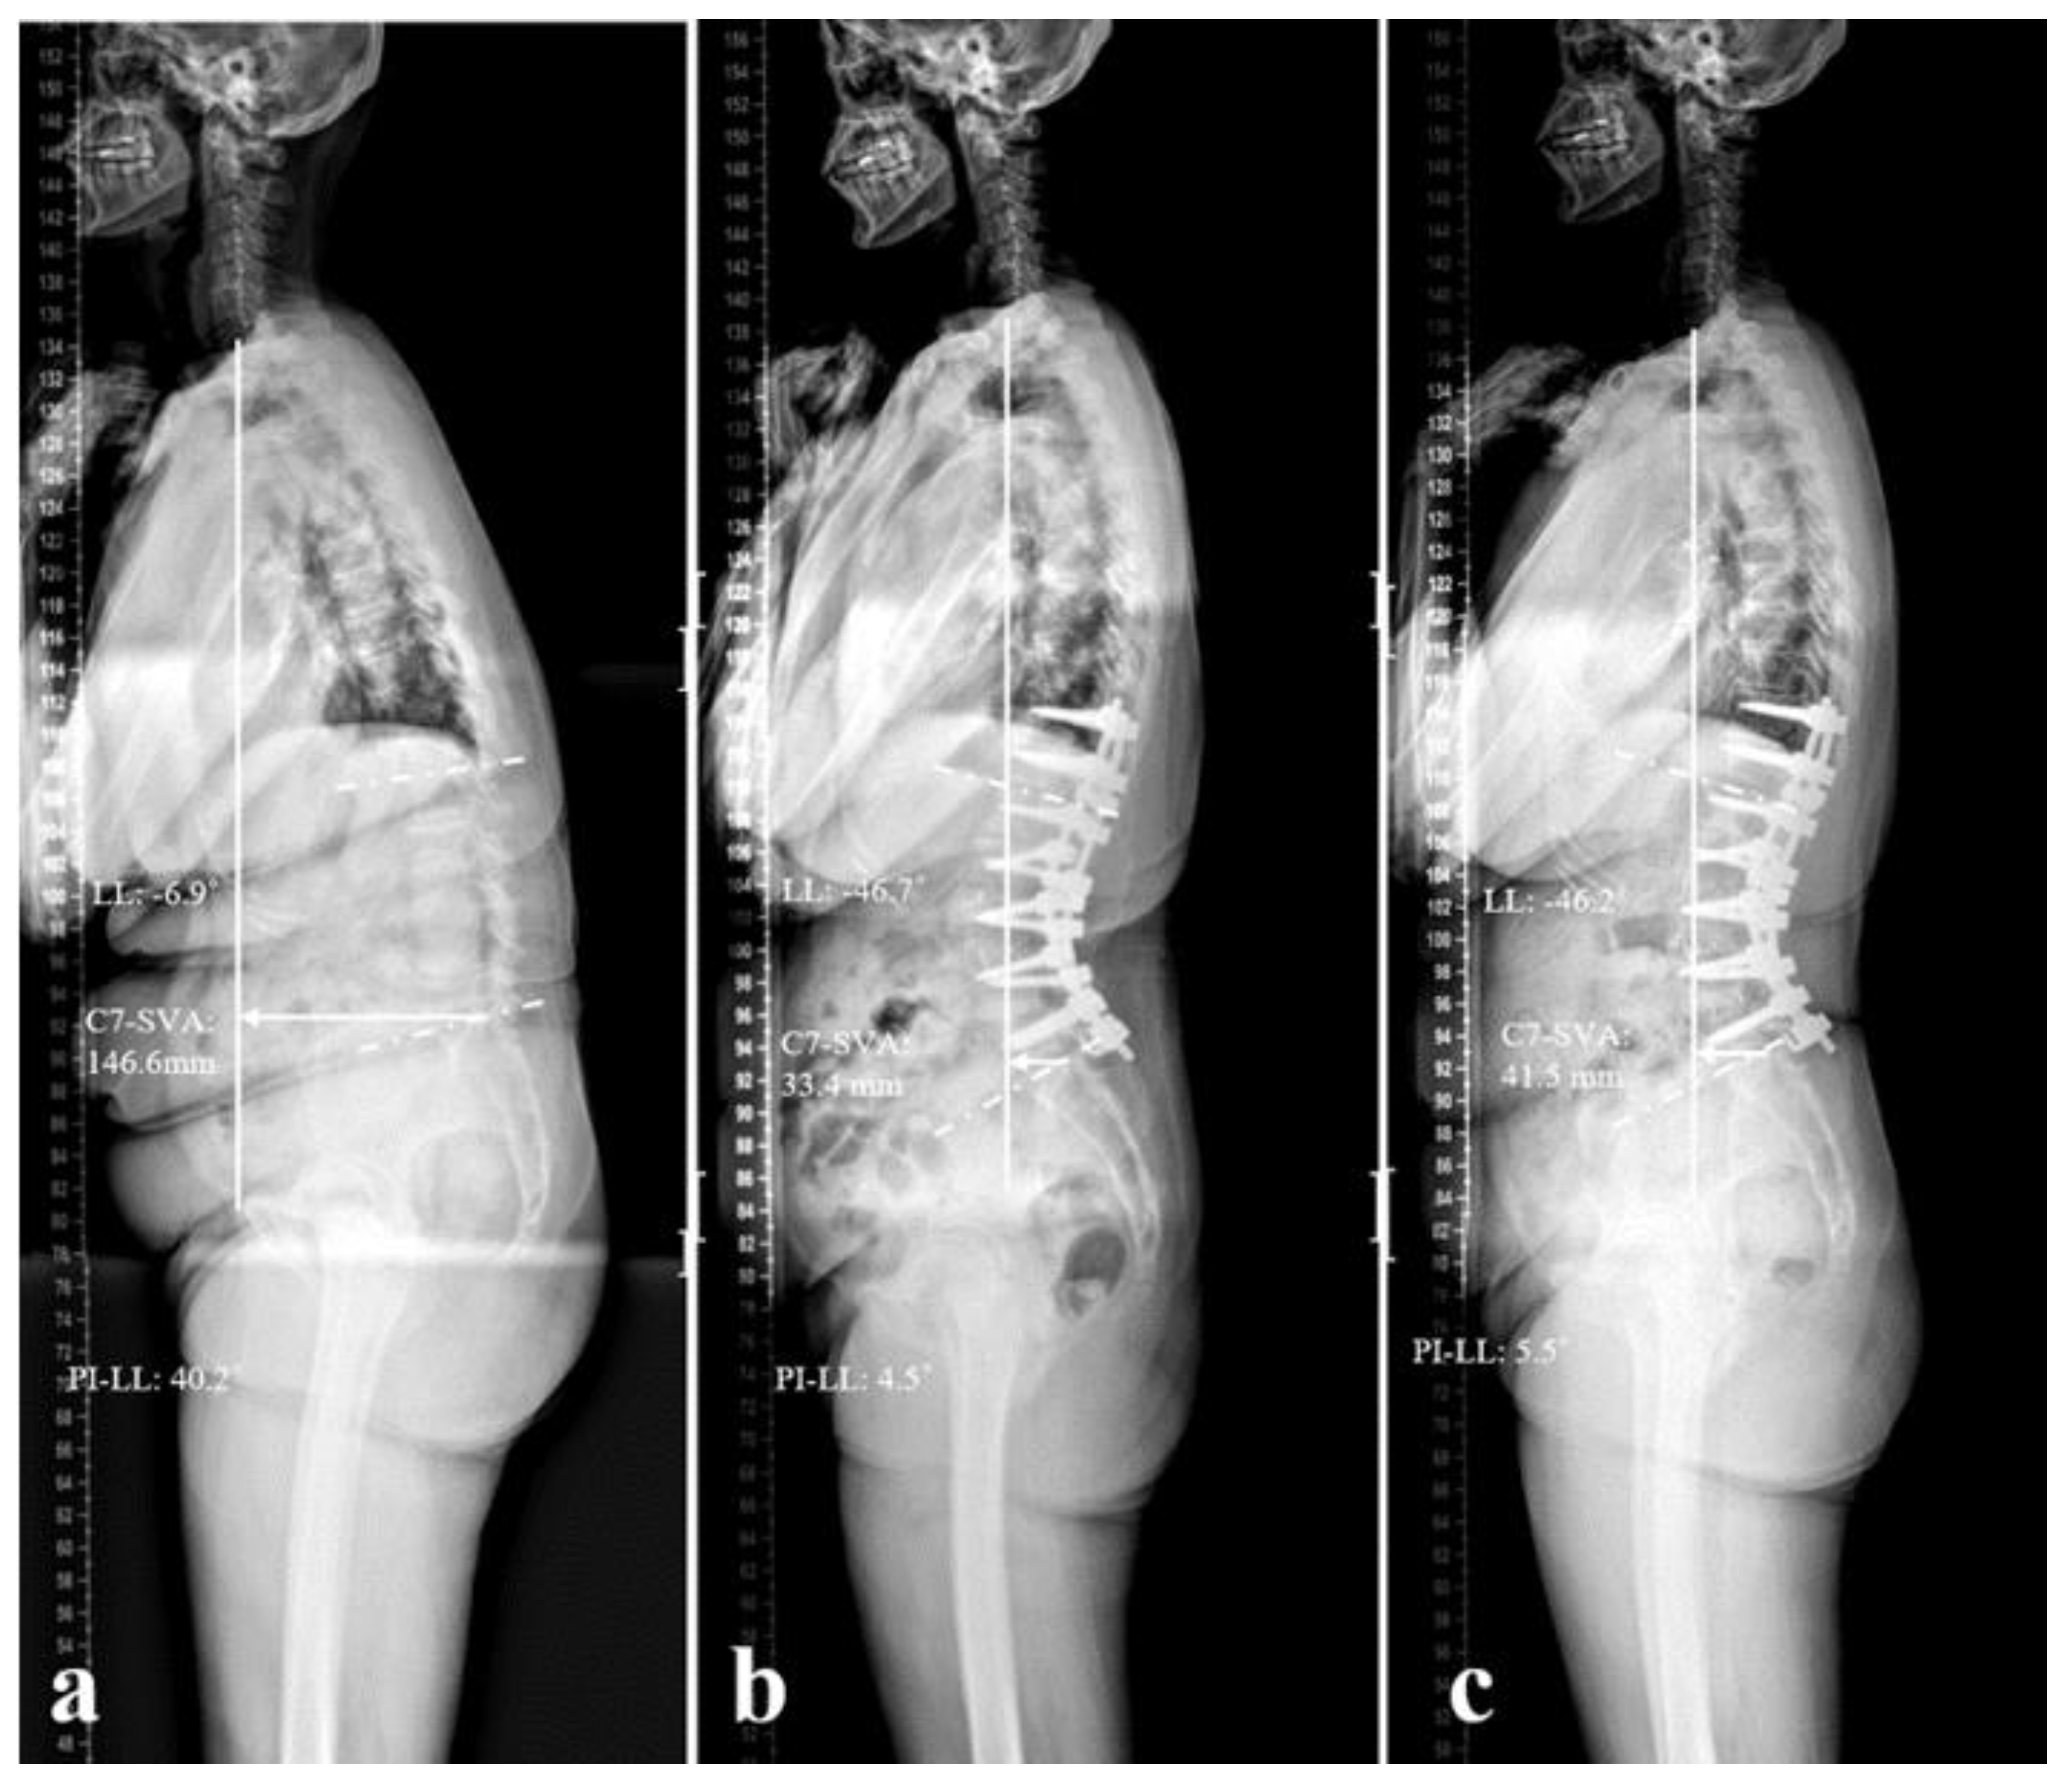

Figure 2. Standing lateral radiographs of a 63-year-old female patient who underwent long-level surgery from T11 to L5, with an L5 laminar hook. (a) Preoperative status, showing significant sagittal imbalance, with a C7-SVA of 146.6 mm, LL of -6.9°, and PI-LL of 40.2°. (b) Postoperative status, showing satisfactory correction; the C7-SVA was 33.4 mm, the LL was -46.7°, and the PI-LL was 4.5°. (c) Two years after surgery, the patient had maintained good sagittal alignment.

The patients in Group I had more severe preoperative sagittal imbalance than those in Group II (C7SVA: 174.6±45.5 vs 52.9±65.1 mm; LL: -11.6±19.3 vs -22.8±23.6º; PI-LL: 44.4±17.5 vs 29.1±21.2º; p<0.05). For both groups, radiographic parameters had improved significantly post-surgery, and there was no significant loss of correction when assessed at the 2 years follow-up. The degree of correction for C7SVA, LL, and PI-LL mismatch in Group I was significantly greater than that in Group II (C7SVA: -136.2±68.6 vs -29.3±75.8 mm; LL: -40.5±15.4 vs -25.4±21.3º; PI-LL: -40.5±15.3 vs -24.8±21.4º; p<0.05). (Table 3)

In the current study, the mean age of patients in both groups was over 70 years, with relatively healthy intervertebral discs at the L5-S1 level and without severe osteoporosis. Given that elderly patients generally exhibit lower levels of physical activity compared to younger individuals, we opted to use a laminar hook or end up at L5 to correct sagittal imbalance during preoperative planning, rather than expanding to S1 or pelvic. Previous studies [11] have demonstrated a clear trend of increased disc degeneration at the L5-S1 level with higher occupational loading. Furthermore, most patients in this study were diagnosed with spinal stenosis accompanied by flatback deformity. The fusion levels were comparable between the two groups, and as a result, the perioperative processes were largely similar. In a previous study, De Jonge et al. al. [12] analyzed the effects of posterior multi-segmented spinal hooks on sagittal correction in patients with idiopathic scoliosis; these authors successfully preserved and restored normal LL by applying spinal hooks. Another study demonstrated that the use of laminar hook for the surgical correction of thoracolumbar fractures could achieve significant correction of local kyphosis and effectively maintain the initial correction [8]. Previous studies showed that the application of a hook could obtain more corrective angles because the laminar hook-rod interface in the distal segment serves as a cantilever beam to achieve better sagittal correction [9]. In accordance with the guidelines generated by previous research [2], during their preoperative planning, surgeons tend to opt for the L5 laminar hook to treat patients with a more severe sagittal imbalance (a larger C7SVA, lower LL, and worse PI-LL mismatch). Postoperatively, the patients in both of our groups achieved significant sagittal balance correction, an outcome that was maintained over the 2 years follow-up period. In addition, we observed that the patients in Group I achieved a greater degree of correction; this was because these patients had more severe preoperative sagittal imbalance. Although we were unable to establish the superiority of the laminar hook for surgical correction, we conclude that laminar hooks can effectively restore severe sagittal imbalance and maintain balance (Figure 2).